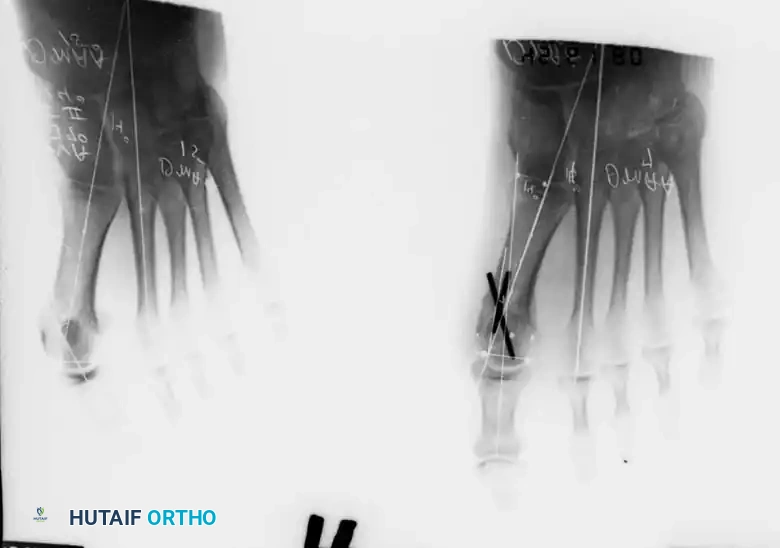

Keller Resection Arthroplasty The Keller procedure combines resection hemiarthroplasty of the fi rst metatarsophalangeal joint with removal of the medial eminence of the fi rst metatarsal (Fig. 78-28). Although removing the base of the proximal phalanx decompresses the joint and mobilizes the hallux, allowing marked correction of valgus, the varus of the fi rst metatarsal is not corrected, and maintaining correction of the valgus of the hallux is diffi cult. Other complications of the Keller procedure have been emphasized in the literature to such an extent (with neither the incidence nor the severity of such complications clearly documented) that the indications for this procedure have been limited severely. In our experience, however, complications are uncommon if patients are selected carefully. Modifi cations in the original technique also have allowed expansion of the indications for the Keller bunionectomy. Candidates for the Keller procedure are patients older than 50 years with moderate-to-severe hallux valgus (30 to 45 degrees); intermetatarsal angles of 13 degrees or less, indicating mild-to-moderate metatarsus primus varus; and pain over the medial eminence with any shoe worn, so the variety of shoes the patient can wear is severely limited. An incongruous fi rst metatarsophalangeal joint caused by

Fig. 78-26 Modifi ed McBride bunionectomy (DuVries; Mann). A, Medial capsule of second metatarsophalangeal joint is sutured to lateral capsule of fi rst metatarsophalangeal joint with interposition of released adductor hallucis. B, Medial capsular resection. C, Confi guration after capsular resection. D, After capsular imbrication, hallux should rest in neutral position or not exceed 5 degrees of varus. E, Postoperative dressing technique (Mann). ( E after Beverly Kessler; courtesy of LTI Medica and The Upjohn Company.) lateral subluxation of the phalanx on the metatarsal head, severe lateral displacement of the sesamoids, and any evidence of degenerative cartilage changes in the joint all are radiographic indications for the Keller procedure. Two modifi cations in technique can expand these indications, however, to include patients with more severe deformities (Fig. 78-29) (but not to include younger patients): fi bular sesamoidectomy and lateral displacement of the fi rst metatarsal. Using these modifi cations, Donley et al. obtained an average 18-degree correction of the metatarsophalangeal angle and an average 6-degree correction of the intermetatarsal angle in 38 patients (50 feet);

Fig. 78-28 A, Anteroposterior radiograph of right foot of 65-year-old patient shows mild-to-moderate deformity and mild degenerative changes at fi rst metatarsophalangeal joint; patient had intraarticular and periarticular symptoms. B, Twelve years after Keller procedure with excision of fi bular sesamoid; note correction of fi rst metatarsal varus and maintenance of enough joint space to allow functional range of motion.

95% of patients were satisfi ed with their results. Patients with 50 degrees or more of valgus of the hallux (18 to 20 degrees of varus of the fi rst metatarsal), complete lateral dislocation of the sesamoids, marked degenerative changes, and severe pronation of the hallux may benefi t functionally and cosmetically from alterations of the standard technique.

D

Fig. 78-29 Severe hallux valgus with bursa formation in 70-year-old woman. A and B, Anteroposterior and lateral clinical photographs of patient’s right foot. C, Correction of deformity by modifi ed Keller procedure. D, Preoperative and postoperative weight bearing radiographs of same patient.